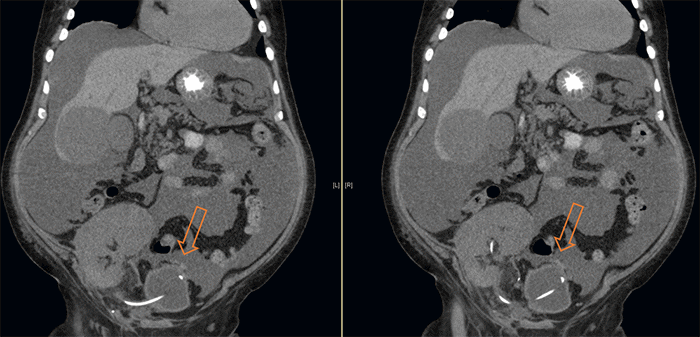

The patient was taken back to the operating room for a retroperitoneal kidney graft exploration through the same transplant incision. The kidney graft appeared well perfused in its entirety, methylene blue dye was instilled in the bladder, and the ureteroneocystostomy anastomosis was intact without leakage. The peritoneum was also intact and bulging into the field due to intraperitoneal fluid, raising concerns for an intraperitoneal process unrelated to the transplant. Therefore, a diagnostic laparoscopy was conducted, revealing significant amounts of blood-free fluid and a clot on the peritoneal wall adjacent to the bladder (between the lateral ligaments). Upon removal of the clot, a defect in the bladder wall was identified, with leakage of methylene blue into the peritoneal cavity confirming bladder perforation (Figure 2). The laparoscope was passed through the defect into the bladder, revealing the presence of a ureteral stent and an intact ureteroneocystostomy. The defect was repaired using a continuous 3.0 V Loc suture, and a drain was inserted. The patient was discharged after eight days. Laboratory tests at discharge showed a white blood cell count of 8100/mL, hemoglobin of 9.3g/dL, hematocrit of 30%, and creatinine of 1.77 mEq/L.

Figure 2. Diagnostic Laparoscopy. Published with Permission

A) During laparoscopic exploration, a clot was found on the intraperitoneal bladder wall, positioned away from the transplant anastomosis. B) Following clot removal, a muscular defect and perforated bladder mucosa were observed. C) A laparoscope was inserted into the bladder to examine the remaining bladder mucosa. D) The bladder defect was closed using an intracorporeal running barbed suture.